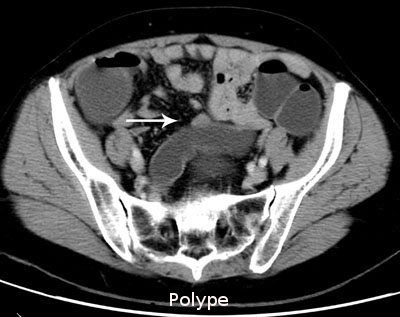

Son indication est essentiellement le diagnostic d'un cancer colorectal et de polypes, il est proposé en alternative à la coloscopie devant des symptômes évoquant un cancer colique, en particulier chez les sujets âgés ou fragiles pour lesquels il est préférable de se dispenser d'une anesthésie générale en première intention. Cette technique permet de faire le diagnostic du cancer et le bilan complet de recherche d'une métastase, en particulier hépatique ou pulmonaire.

Lésion villeuse du segment distal du sigmoïde (images 1, 2 et 3)